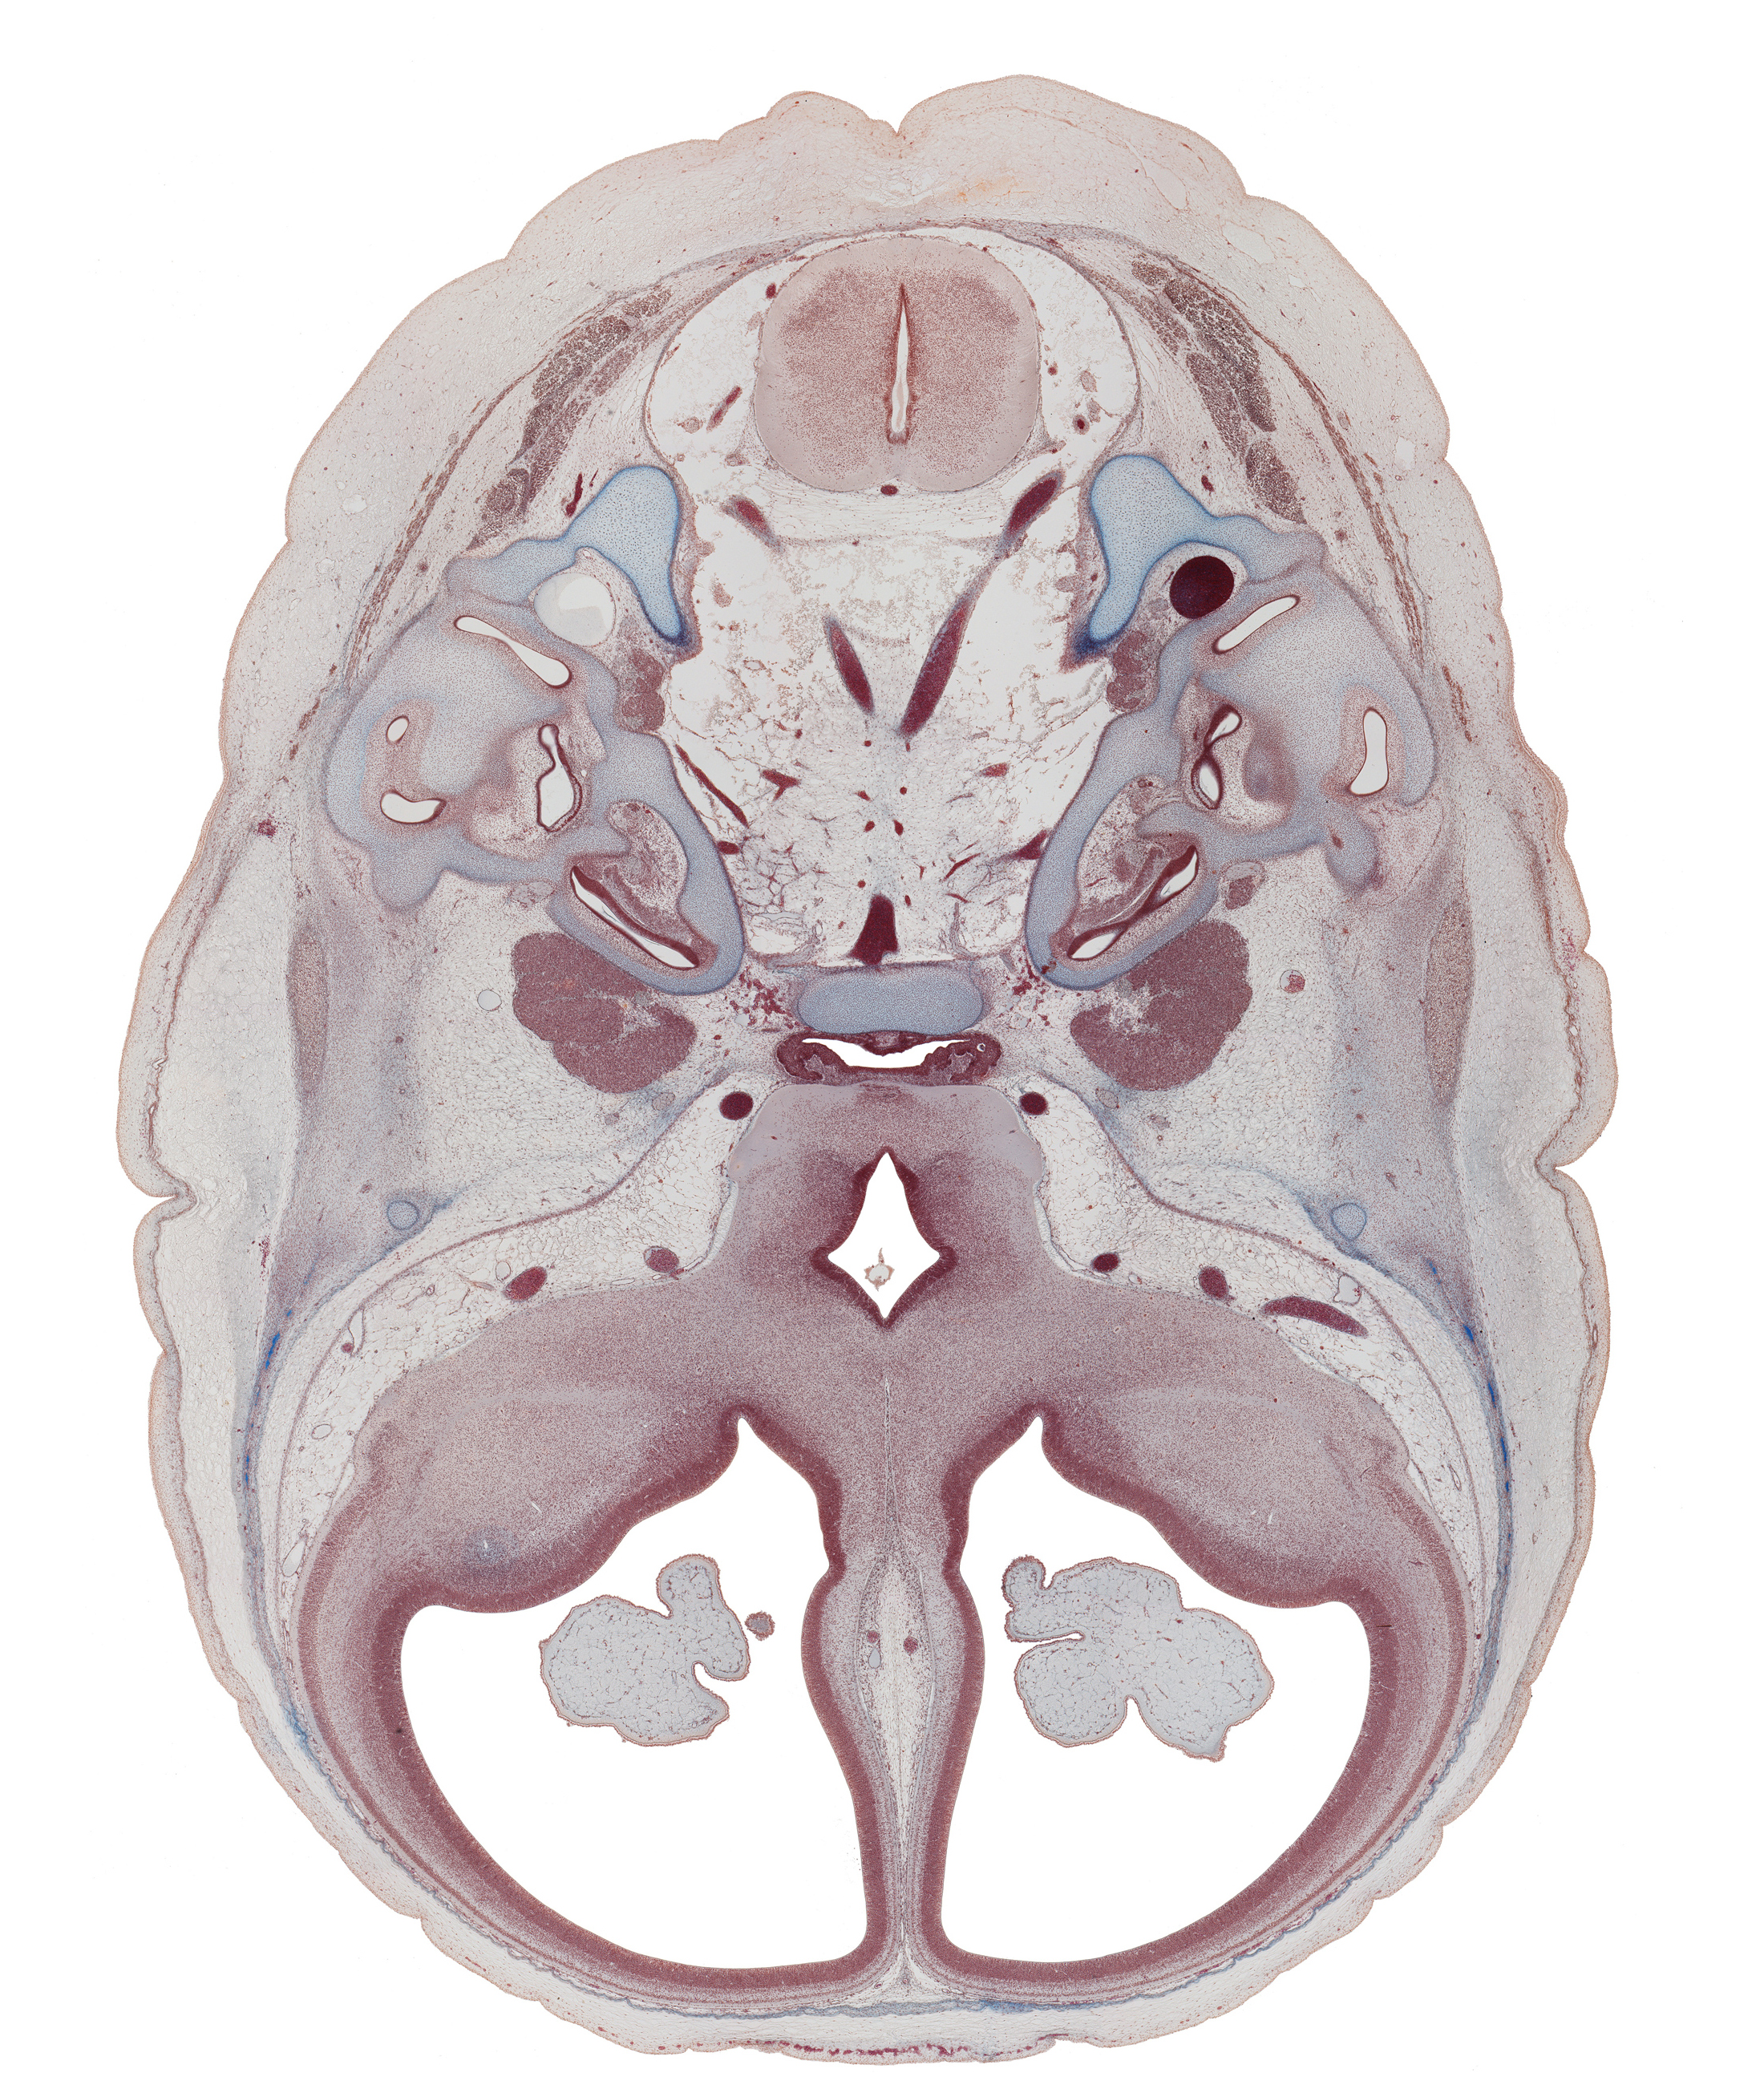

Carnegie Embryo #9226 | Location: 57-01-01

Keywords: abducens nerve (CN VI), adenohypophysis (intermediate part), anterior spinal artery, basilar artery, basisphenoid, caudal part of medulla oblongata, cochlear duct, foramen magnum, hypothalamus, junction of cochlear duct and saccule, junction of internal jugular vein and sigmoid sinus, labrynthine artery, lateral semicircular duct, lateral ventricle, middle cerebral artery, neurohypophysis, optic groove, optic tract, piriform cortex (paleopallium), posterior semicircular duct, superior ganglion of glossopharyngeal nerve (CN IX), superior ganglion of vagus nerve (CN X), third ventricle, vertebral artery

Source: The Virtual Human Embryo.